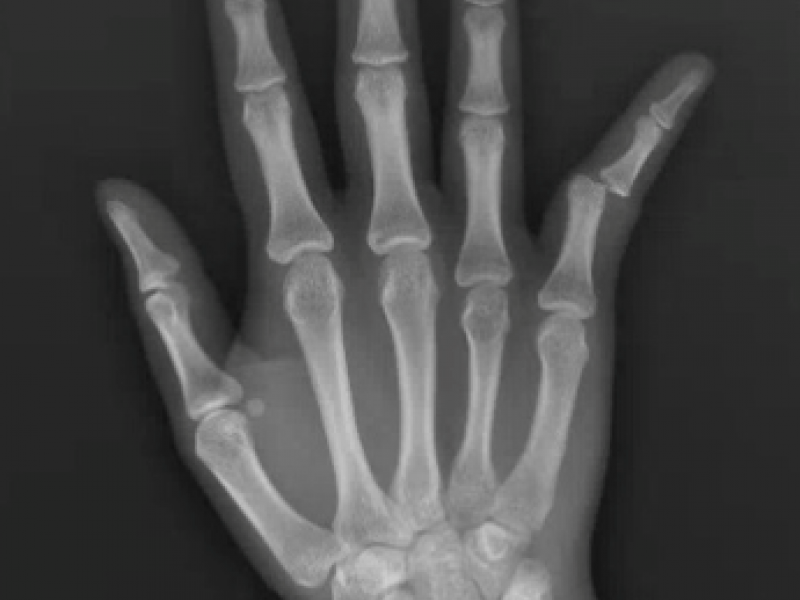

A 13 year old female presents with right 5th digit pain and